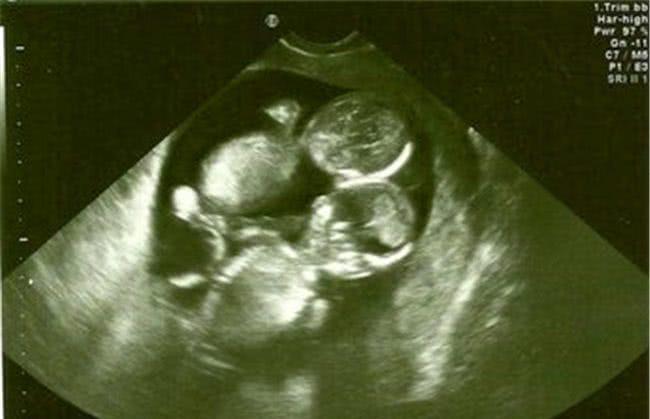

知道去年年底,陈女士的月经一直不来,用验孕棒一查才发现怀孕了,她和老公喜极而泣。对于这个来之不易的胎儿,家人给出了足够的重视,婆婆从乡下赶过来照顾她。怀孕三个月的时候查出是双胞胎,这让全家人都兴奋不一样,都说车女士厉害,不怀孕则罢,一怀孕就是双胞胎,给家里挣足了面子,婆婆逢人就夸儿媳。

然而怀孕第五个月排畸检查却让全家人掉入了谷底,医生告知这是一个连体婴儿,脑袋连在一起了,建议立马做引产手术。不然生下来不但拖累家庭,对孩子也是一种不负责。车女士和老公瞬间感觉到整个天都塌了,此时孩子已经有胎心了,陈女士能明显感觉到宝宝强有力的跳动。

半个小时后,子宫被划开了,医生却惊喜欢呼,双胞胎并没有连体,是一对龙凤胎,十分健康。车女士听后顿时忍不住哭泣起来,心里的委屈一下子全部控制不住发泄出来,没有人知道整个孕期她是怎么过来,承受了多大的心理压力。

医生说做四维彩超的时候,刚好两个胎儿的头紧紧靠在一起,所以被误认为是连体婴,没想到却是兄妹情深,相互相依。产房外的家属得知后也是相拥而泣,爸爸更是对两个更出生的婴儿说,以后一定要好好孝顺你妈,是她的坚持才有你们俩。